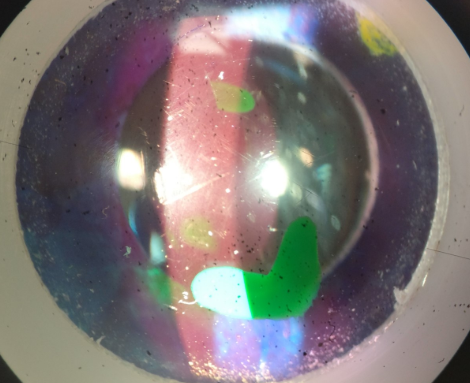

There are lesions in the cornea shown below. What layer of the cornea is this

Epithelium.

what layer of the cornea are the arrows pointing to

epithelium

which layer of the cornea is the green lesion located in?

endothelium